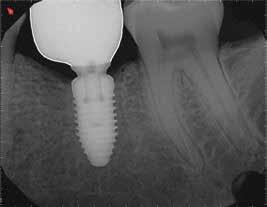

1. a–f ábrák: A cingulumon keresztül gömbfúróval kialakított hozzáférés a trepanációs kavitás labiális irányba történő túlzott mértékű kiterjesztését eredményezheti, és ez lényegesen növelheti a perforáció esélyét (a). A guttapercha átsejlik a lágyrészek alatt (b). Klinikailag igazolt perforáció (c). A preoperatív sagittális irányú CBCT-szeleten jól látható a labiális perforáció (d). Labiális irányú perforáció (fekete nyíl; e). A tényleges gyökércsatorna (piros nyíl; f).

A frontfogakban történő hozzáférési nyílás kialakítása

A frontfogakban a hozzáférési nyílás kialakítását hagyományosan a fogak linguális vagy palatinális felszínén, a cingulumon keresztül egy gömbfúró segítségével kezdjük. A linguálisan elhelyezkedő kiemelkedés teljes eltávolítása, továbbá a pulpaszarvak teljes feltárása egy háromszög alakú hozzáférési nyílást eredményez. 7 Ezt a módszert a fogak esztétikai megjelenésének megőrzése érdekében fejlesztették ki. Ez azonban időnként a saját foganyag indokolatlan eltávolításával, a trepanációs kavitás labiális irányba történő túlzott kiterjesztésével, perforációval, valamint a fog kritikus helyen, a pericervikális dentin (PCD) területén történő meggyengítésével jár (1. a–f és 2. a-b ábrák). 19 Felmerült, hogy a pericervikális dentin rendkívül fontos szerepet játszik a rágóerő gyökerek irányába történő továbbításában, és elképzelhető, hogy a gyökérkezelt fogak hosszú távú megtartása szempontjából a legfontosabb tényező az ép pericervikális dentin megőrzése lehet. 20 A cingulumon keresztül történő hozzáférési nyílás

kialakítása során fennáll a fog labiális irányú perforációjának veszélye, mivel ilyenkor a foganyag elvételét labiális irányú fúrótartással kezdjük. Nemrégiben újragondolták a